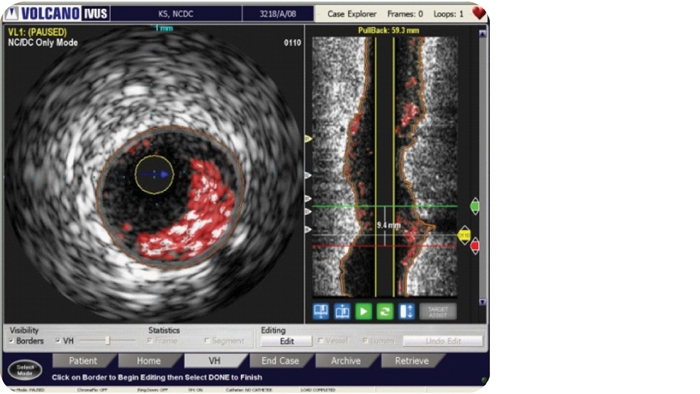

VH IVUS imaging provides a colorized tissue map of plaque composition with automated lumen and vessel measurements.* VH IVUS technology uses advanced, proprietary spectral analysis techniques to classify plaque into four tissue types with 93-97% accuracy.1

VH IVUS provides a colorized tissue map of plaque composition for complete lesion assessment. Based on more than 15 years of research and 350 scientific publications, including the landmark PROSPECT trial, VH IVUS can assist you with lesion risk assessment, identification of necrotic core for optimizing stent placement, and monitoring of transplant patients for cardiac allograft vasculopathy.

For complete lesion assessment, VH IVUS provides a colorized tissue map of four tissue types:

VH IVUS provides automatic border contours for full segment analysis.

VH IVUS may help assess lesion risk: